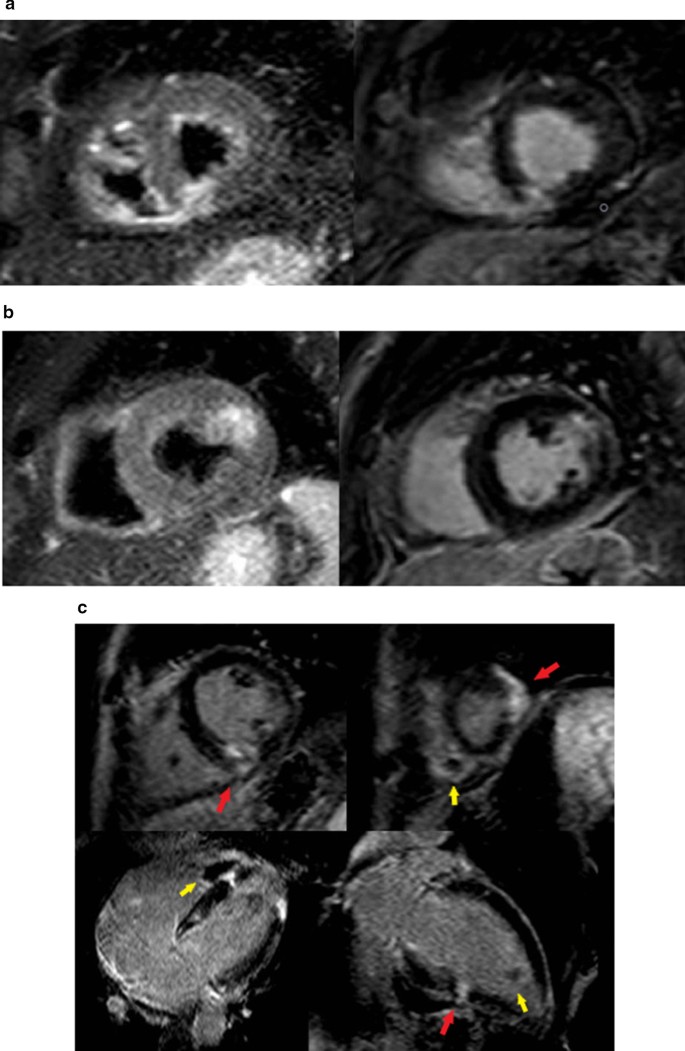

The CMR was performed at a median of 12 days. LGE demonstrated transmural enhancement in 93 cases (77.5%), and subendocardial enhancement in 19 (15.8%). Eight patients, (6.7%) had both types in two distinct regions (Fig. 2). Almost three-quarters of the patients (69.8%) presented with a small infarction on LGE, defined as enhancement in one or two LV segments. The most frequent infarct location was the inferolateral wall (Table 2; Fig. 2).

CMR images. a Focal transmural inferoseptal acute myocardial infarction. Left: T2 short tau inversion recovery (STIR) short-axis image showing focal transmural edema. Right: Late gadolinium enhancement (LGE) CMR short-axis corresponding image showing transmural hyperenhancement. b Anterolateral subendocardial acute myocardial infarction. Left: T2 STIR short-axis image showing focal subendocardial edema. LGE short-axis corresponding image showing focal subendocardial hyperenhancement. c Presence of three distinct focal myocardial infarctions: lateroapical, septomedial and inferomedial (red arrows), with images suggestive of thrombus in both ventricles (yellow arrows). LGE images (upper: 2 short-axis views; lower: 4-chamber and 2 chamber views) showing the 3 foci of enhancement. LGE late gadolinium enhancement